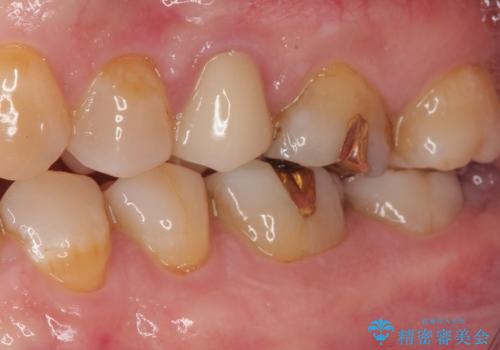

最新の症例

Latest cases